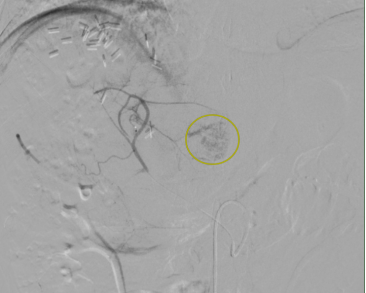

发现本次复发肿瘤病灶位于肝尾状叶

其位置位于腹腔深部

且后方为腹主动脉这一人体重要血管

肝尾状叶肿瘤病灶